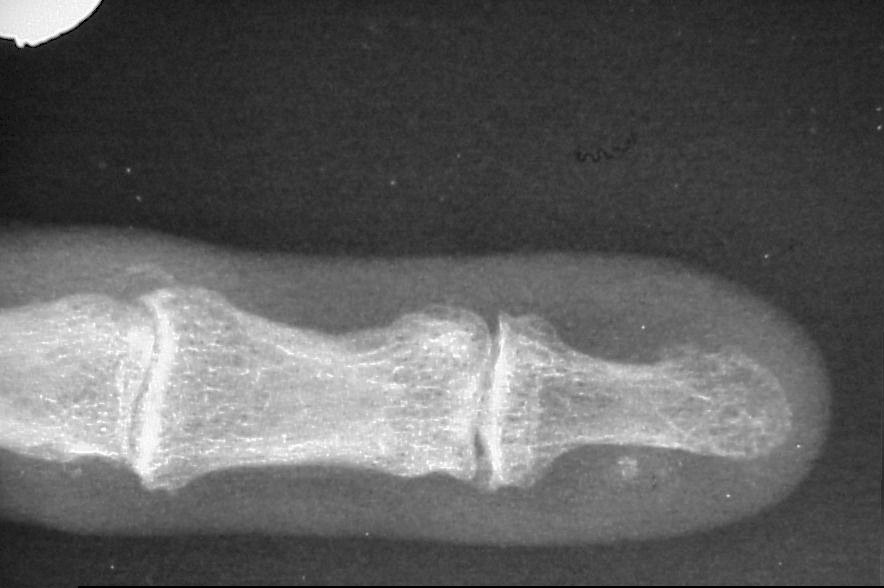

Case 1: Mass arising a year after nail bed excision and skin graft for nail bed squamous cell carcinoma.

Xrays show discrete calcification in the area, consistent with heterotopic ossification.